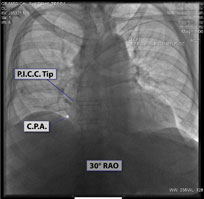

2. On inspiration upright CXR, the tip of VAD is ideally at C.A.J. See Fig.# 09 - Gallery.

3. Chest x-ray rotation tissues: Not infrequently, the chest x-ray will be rotated causing the right cardiac margin to deviate from its normal AP appearance. In such situations, depending on the degree of rotation, an estimation of the SWEET SPOT™ is all that may be possible. In such circumstances, the right cardiophrenic angle is the most reliable anatomic landmark. Since the right atrium is immediately cephalad to a normally positioned right cardiophrenic angle, a reliable estimation of acceptable catheter tip location is still possible. The height, and consequently the width of the rectangular Sweet Spot™ box will be less exact and therefore a relatively short catheter tip position may require a non- rotated chest x-ray to confirm an acceptable location. Aim for the right atrium. See Figs. T.1, T.2, and T.3.

17. “A good use of carinal landmarks for catheter tip location- right sided White Out.” See Fig. T.4 - Carina.